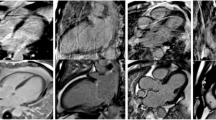

Figure 2 illustrates the image quality for a paired 0.55 T and 1.5 T breath-held study in a patient with a severe cardiomyopathy. Additional file 2 illustrates the image quality for a paired free-breathing study in a patient with sickle cell disease and a large pericardial effusion. The L1-SPIRiT reconstruction used for the free-breathing acquisition results in similar image quality between 0.55 T and 1.5 T.

Regional wall motion abnormalities were identified in nine subjects with a total of 72 abnormal segments. Sector-wise comparison of the extent of regional wall motion abnormalities revealed a close correlation between the 0.55 T and 1.5 T in the identification of abnormalities (kappa 0.99). Figure 5 illustrates the appearance of a thinned chronic infarction and apical aneurysm on 0.55 T and 1.5 T scanners. Additional file 3 demonstrates example cine imaging movie of the wall motion abnormality on both CMR systems. This patient had an aortic bioprosthetic valve from a prior surgery, and the artifact is modestly improved using 0.55 T.

Example wall motion abnormality at 0.55 T and 1.5 T. Breath-held cine images from 0.55 T (top row) and 1.5 T (bottom row) are provided for a patient with a chronic myocardial infarction and apical aneurysm resulting in regional wall motion abnormality. Videos of wall motion abnormality are provided in Additional file 3